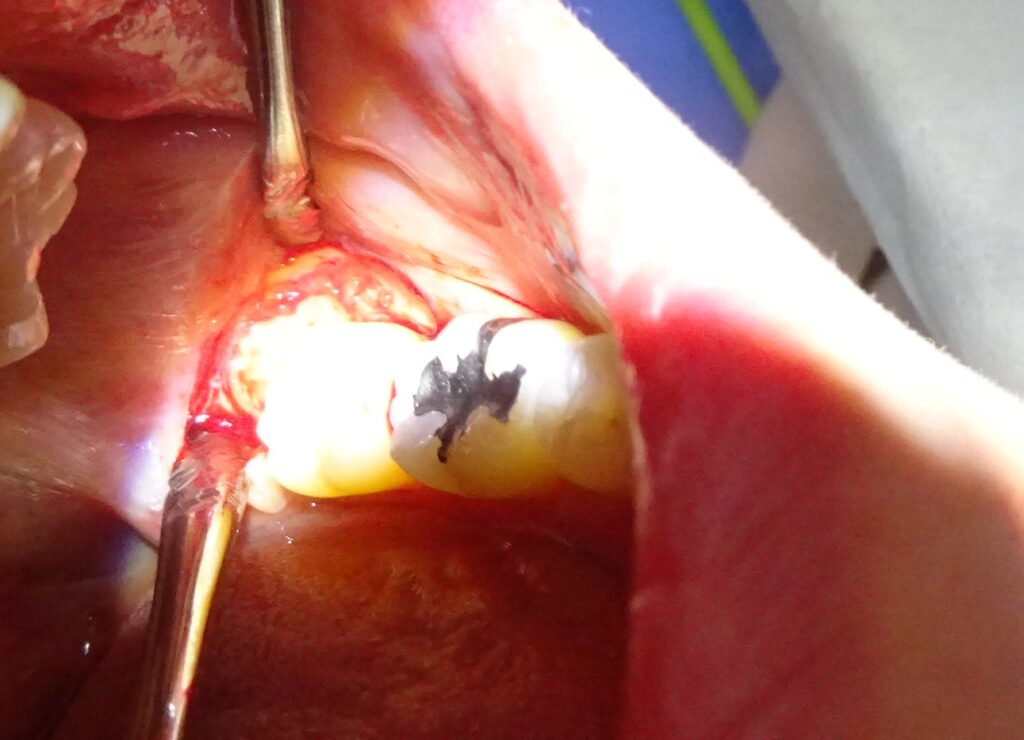

まずは親知らずは歯茎の下に隠れている状態なので、歯茎を切開していきます。

親知らずの周りの骨を最小限削っていき、抜いていくスペースを作ります。

そこから親知らずの頭を輪切りにするように切断して取り除き、最後に根っこの部分を慎重に抜いていきました。

傷口を縫合し抜歯終了です。